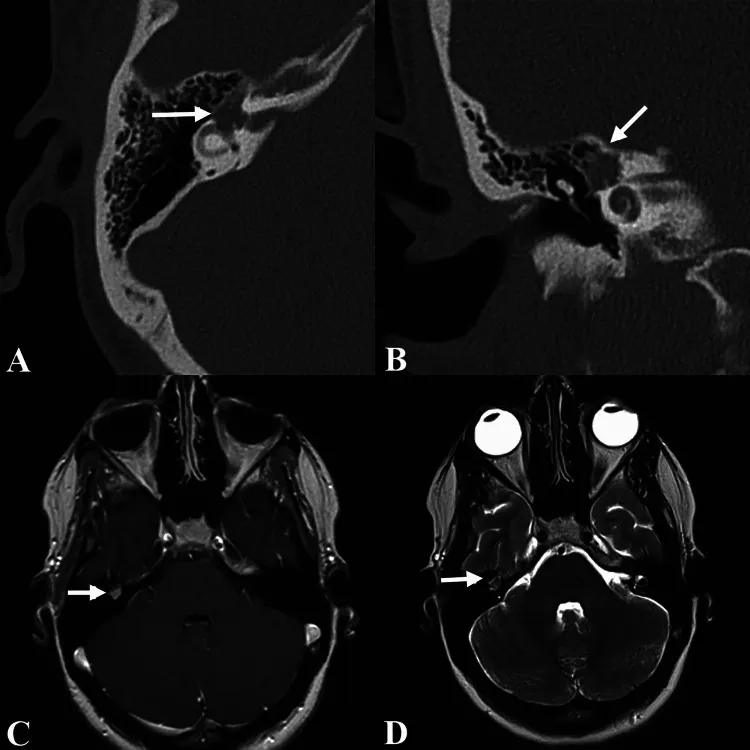

影像学检查显示右侧颞骨有一强化、溶骨性面神经区肿块,中心位于膝状神经节,延伸至面神经迷路段及前庭,肿块内未见明显钙化(图1)。根据其均匀强化、膝状神经节周围面神经增粗、无钙化等影像学特征,最初考虑为面神经瘤。经讨论,治疗方案包括定期影像学随访观察与手术干预。考虑到面肌无力可能进展的风险,患者选择接受手术治疗。

图1.显示右侧膝状神经节周围肿块的影像学图片。(A)轴位及(B)冠状位计算机断层扫描图像,以及(C)轴位T1加权增强后及(D)轴位T2加权磁共振图像,显示右侧膝状神经节周围肿块(箭头所示)。